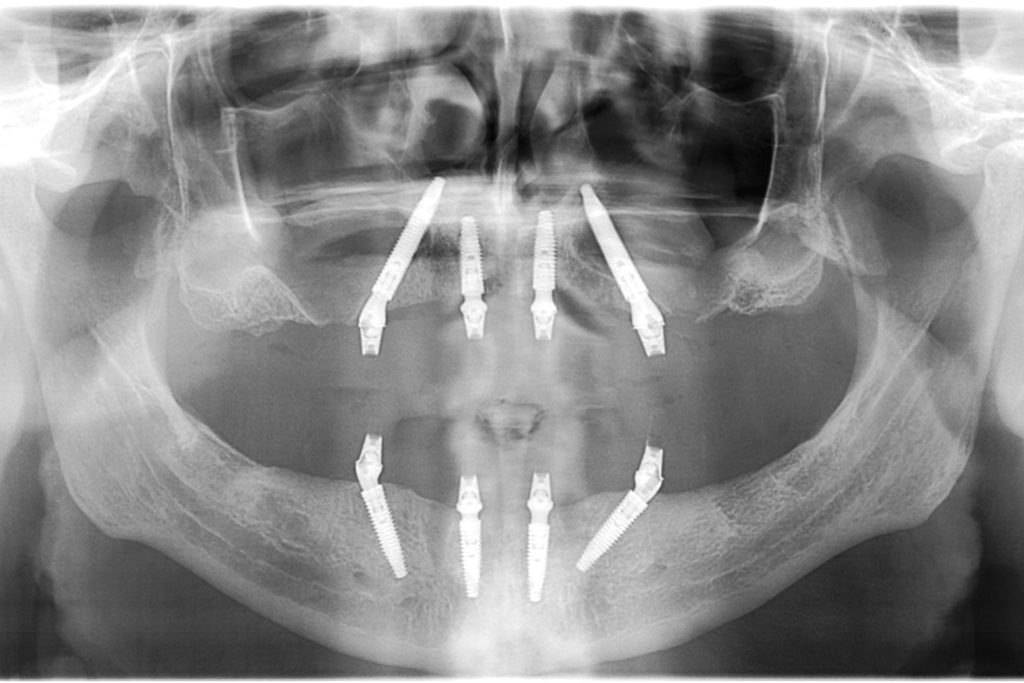

Double All-on-4 surgery Belgrade

Control Panoramic X ray image right after surgery showing Neodent GM Helix implants